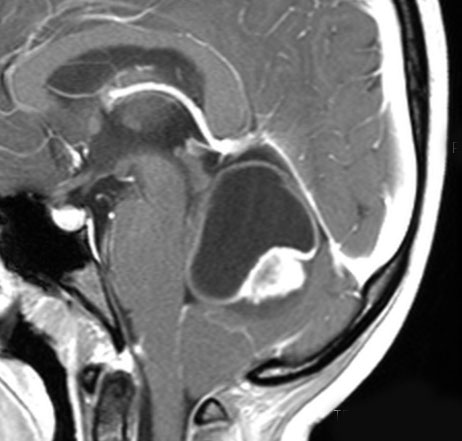

左は術前,右は手術直後のMRIです。このビデオを見て,およその手技の順番のみ把握して下さい。